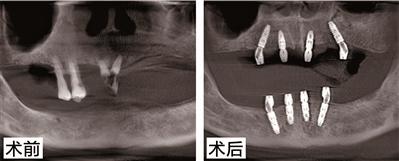

陳伯今年76歲了,也是德國種植牙技術(shù)的親身體驗(yàn)者之一。他之前患有牙周病,牙齒全口缺失,在醫(yī)生的指導(dǎo)下采用了德系A(chǔ)ll-on-N種植技術(shù)和種植技術(shù),種牙到現(xiàn)在3年了,牙齒依然堅(jiān)固如初。為此,陳伯感嘆道:“缺牙這么多年,沒想到是柏德幫自己實(shí)現(xiàn)了多年的愿望。我記得種完牙當(dāng)天就能正常吃飯。一把年紀(jì)還能再次享受口福,這種感覺真好?!睋?jù)悉,百蟹宴當(dāng)天,陳伯將應(yīng)邀分享種牙感受,并與現(xiàn)場觀眾比拼吃大閘蟹,展示種牙后的果。種植牙PK大閘蟹,究竟誰能勝出呢,我們拭目以待!

針對陳伯的種牙情況,柏德口腔天河院長薛啟明表示,All-on-N種植技術(shù)和種植技術(shù)可以說能很好地解決多顆牙缺失或者全口無牙問題,尤其是對于上了年紀(jì)又怕痛的缺牙患者。電腦三維模擬成像技術(shù)能在手術(shù)前,地計(jì)算種植點(diǎn)位、植入角度和深度,再通過3D種植導(dǎo)板植入,避開神經(jīng)系統(tǒng)和血管,實(shí)現(xiàn)種植。整個(gè)手術(shù),在麻醉儀的幫助下,患者幾乎沒有任何不適。德系A(chǔ)ll-on-N種植技術(shù)還有一個(gè)好處就是,只需要花少量的錢,就能恢復(fù)整口牙的咬合果,這對患者來說無疑是實(shí)惠的。